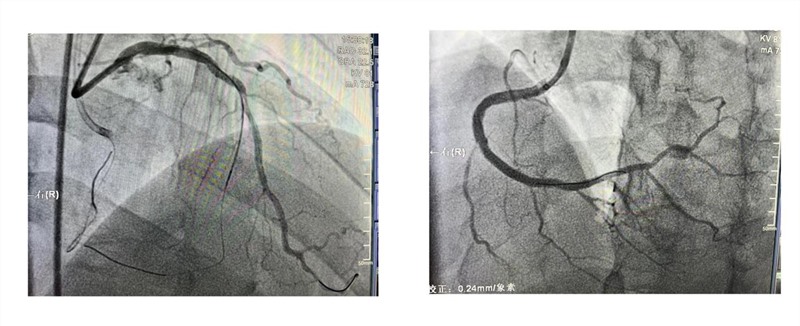

患者男,48岁,本次因急性胸痛入住渝中心血管内科,确诊为急性非ST段抬高型心肌梗死,其基础合并高血压、糖尿病等多种高危因素。急诊冠脉造影提示:右冠优势,左主干+三支病变,回旋支及右冠主支均闭塞,左主干-前降支重度狭窄,程度大于90%。心脏彩超提示左右心室均增大,下壁及后壁搏幅弥漫降低,射血分数降低,患者生命岌岌可危。从病变解剖建议患者外科搭桥,后患者多家医院咨询,拒绝外科治疗,强烈要求在我院进行介入治疗。

▲冠脉造影结果